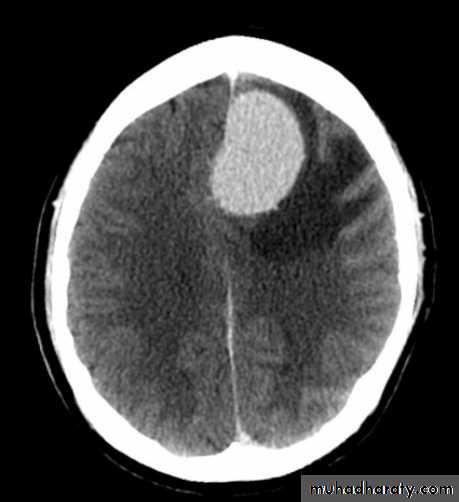

Meningioma

Benign tumor arise from the arachnid cells of the meningeal covering of the brain are most common primary intracranial neoplasm

Usually present in middle age female

it is well defined extra axial , located mainly at the convexity of the skull periphery

CT finding

meningioma presented as isodense area or slightly hyper density area with surrounded crescent of hypo density ( csf cap ) post contrast injection the lesion enhance homogeneously with enhancing Dural tail .

20 % show calcification

hyperostosis & thickening of the near by bony part of the skull & diplioc space .

it may be associated with little or no peri focal edema .

if the lesion associated with central necrosis with large perifocal edema meningio sarcoma should be excluded .